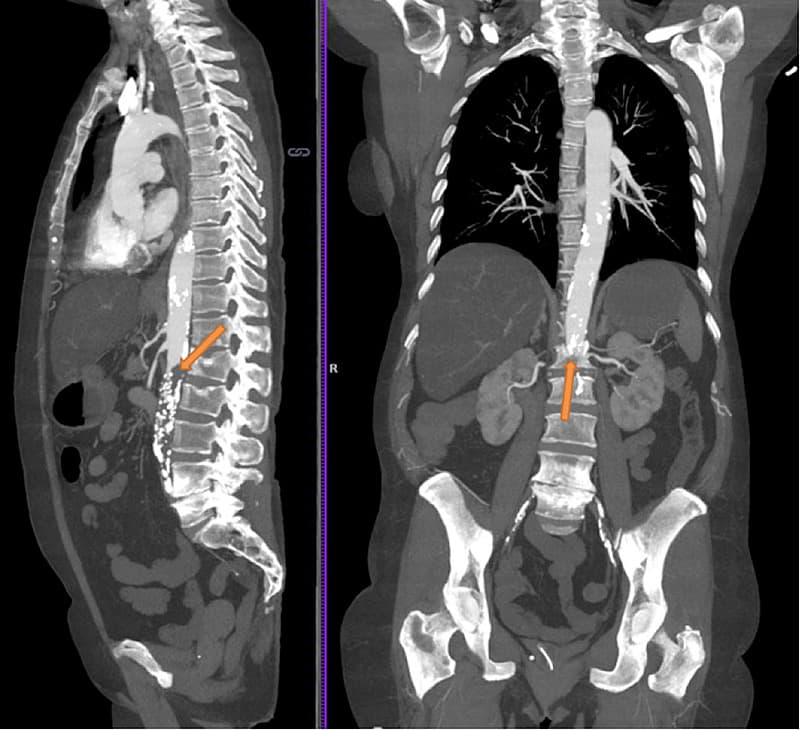

En CT af thorax og abdomen viste manglende kontrastopladning i aorta og afslørede total okklusion af aorta abdominalis distalt for nyrearterierne. Radiologisk vurderede man, at tromben var akut opstået.